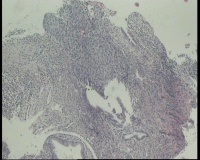

请老师 看看,宫颈活检,宫颈CINIII累腺局灶早期浸润还是直接报宫颈鳞癌?

鳞状上皮全层异型增生,局灶基底膜不清,请老师看看巢状分布的是累腺还是浸润?

CIN3累腺,不排除有浸润的可能。

有浸润,鳞癌